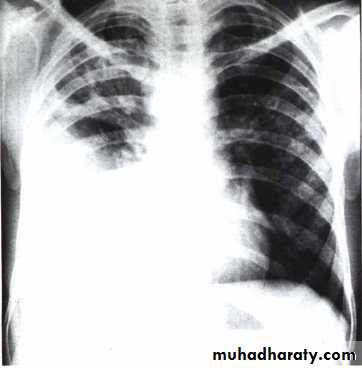

Unilateral effusionDiseases of the Pleura Dr.Mustafa Nema. Baghdad College of Medicine 2013

Bilateral effusion

Chest X ray: The pleural fluid accumulates in the most dependent part of the thoracic cavity

The normally sharp posterior costophrenic angle is obliterated.

Upper surface is meniscus-shaped (meniscus sign).

Around 200 mL of fluid is required in order for it to be detectable

on a PA chest X-ray

The amount of pleural effusion may be small, large or massive.